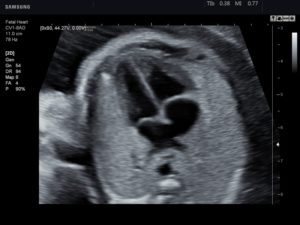

Эхокардиография плода

Эхокардиография плода (фетальная эхокардиография) – специальная ультразвуковая методика, позволяющая в процессе беременности исследовать морфологические и функциональные особенности сердца плода. Позволяет еще до рождения, неинвазивно выявлять врожденную патологию сердца. Обычно выполняется на 18-24 неделе гестации.

ЭхоКГ плода дает возможность оценить состояние полостей сердца, межпредсердных перегородок сердечных клапанов, магистральных сосудов. Применяется для пренатальной (дородовой) диагностики врожденных пороков сердца и нарушений сердечного ритма у плода, что дает возможность оптимально спланировать дальнейшую тактику их лечения.

Наиболее достоверные результаты можно получить на 18-24 неделе беременности. При исследовании используется трансабдоминальный доступ, однако в случае необходимости на сроке гестации менее 18 недель ЭхоКГ может быть выполнена трансвагинальным способом.

Процедура длится около 30-40 минут и по методике проведения напоминает обычное УЗИ.

Во время процедуры эхокардиографии плода беременная должна быть спокойна и расслаблена; возможно, по рекомендации врача за несколько дней до планируемого исследования ей придется прекратить прием определенных лекарственных препаратов.

Стандартное эхографическое исследование включает оценку четырехкамерного среза сердца (положения сердца в грудной полости, строения желудочков и предсердий, сформированности межжелудочковой и межпредсердной перегородок, движений створок митрального и трикуспидального клапанов), главных артерий (взаиморасположение и диаметр аорты и легочного ствола), характеристик сердечной деятельности (ЧСС, ритмичности предсердно-желудочковых сокращений). С протоколом эхокардиографии плода в обязательном порядке должен быть ознакомлен акушер-гинеколог, наблюдающий беременность, который прокомментирует женщине результаты диагностики, объяснит все имеющиеся риски.

Качество ультразвуковой визуализации зависит от уровня квалификации и опыта специалиста, типа используемого оборудования, срока гестации, положения плода, мало- или многоводия, толщины подкожно-жирового слоя на передней брюшной стенке беременной.